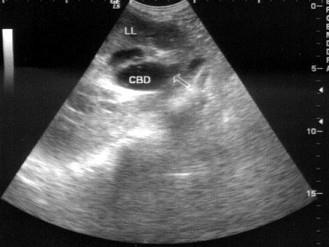

问题 患者女53岁,上腹部疼痛不适半年余,皮肤、巩膜黄染进行性加重。B超检查如图所示,根据超声声像图诊断为?(?)

选项 A.胆总管下段癌 B.胰头癌 C.胆总管炎性狭窄 D.胆总管结石 E.胆总管蛔虫

答案 A